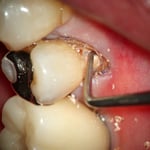

左 :歯の根元に生じた虫歯です。(茶色の部分)この状態では、どこまでが歯なのか歯肉に覆われていてわかりません。通常、このままプラスティックを充填してしまうことが多いようです。

虫歯を丁寧に除去すると、かなり深い場所まで虫歯があることがわかります。虫歯を完全に除去し、接着操作のために酸で歯面を処理します。特殊なセメントをキャリアし、象牙質に緊密な絆創膏を貼ります。(周囲の象牙質の耐酸性が向上する効果もあります)この症例の場合、欠損部にグラスファイバーのポストをたてました。(縦方向の力に耐えるため)プラスティックを充填して完了です。